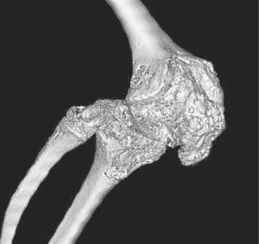

При прогрессировании заболевания возможно развитие значительного сужения суставных щелей и анкилозов в периферических суставах (фото 14).

![]() | ![]() | ![]() |

Фото 14. Анкилоз коленного сустава при ЮАС. КТ: 3D-реконструкция [4].